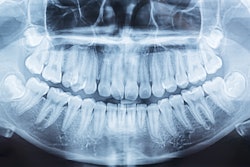

Planmeca and Bego announced a collaboration in which Bego's materials have been validated for the Planmeca Creo C5 dental 3D printer. Image courtesy of Planmeca and Bego.

Dental equipment manufacturer Planmeca has partnered with 3D printing technology provider Bego.

The collaboration will enable Planmeca's Creo C5 dental 3D printer to use Bego's materials for making same-day dental restorations.